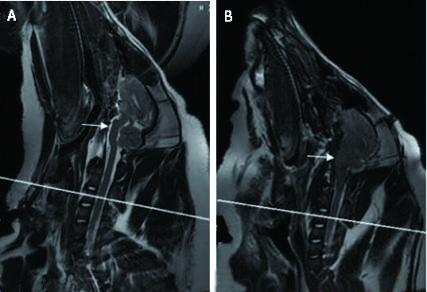

头颅MRI(T2WI)扫描后显示:血肿位于左侧脑实质内,左侧侧脑室受压变窄,中线向右侧偏移。造模前桥脑前池存在,为线条状高信号影;造模后桥脑前池消失,为线条状高信号影消失,提示脑组织移位,脑干受压(图 1)。

| C3水平(A):造模前脑池存在,为线条状高信号影;(B)造模后桥脑脑池消失,为线条状高信号影消失,提示脑组织移位,脑干受压(白色箭头示) 图 1 头颅MRI T2WI Fig 1 Head MRI T2WI |